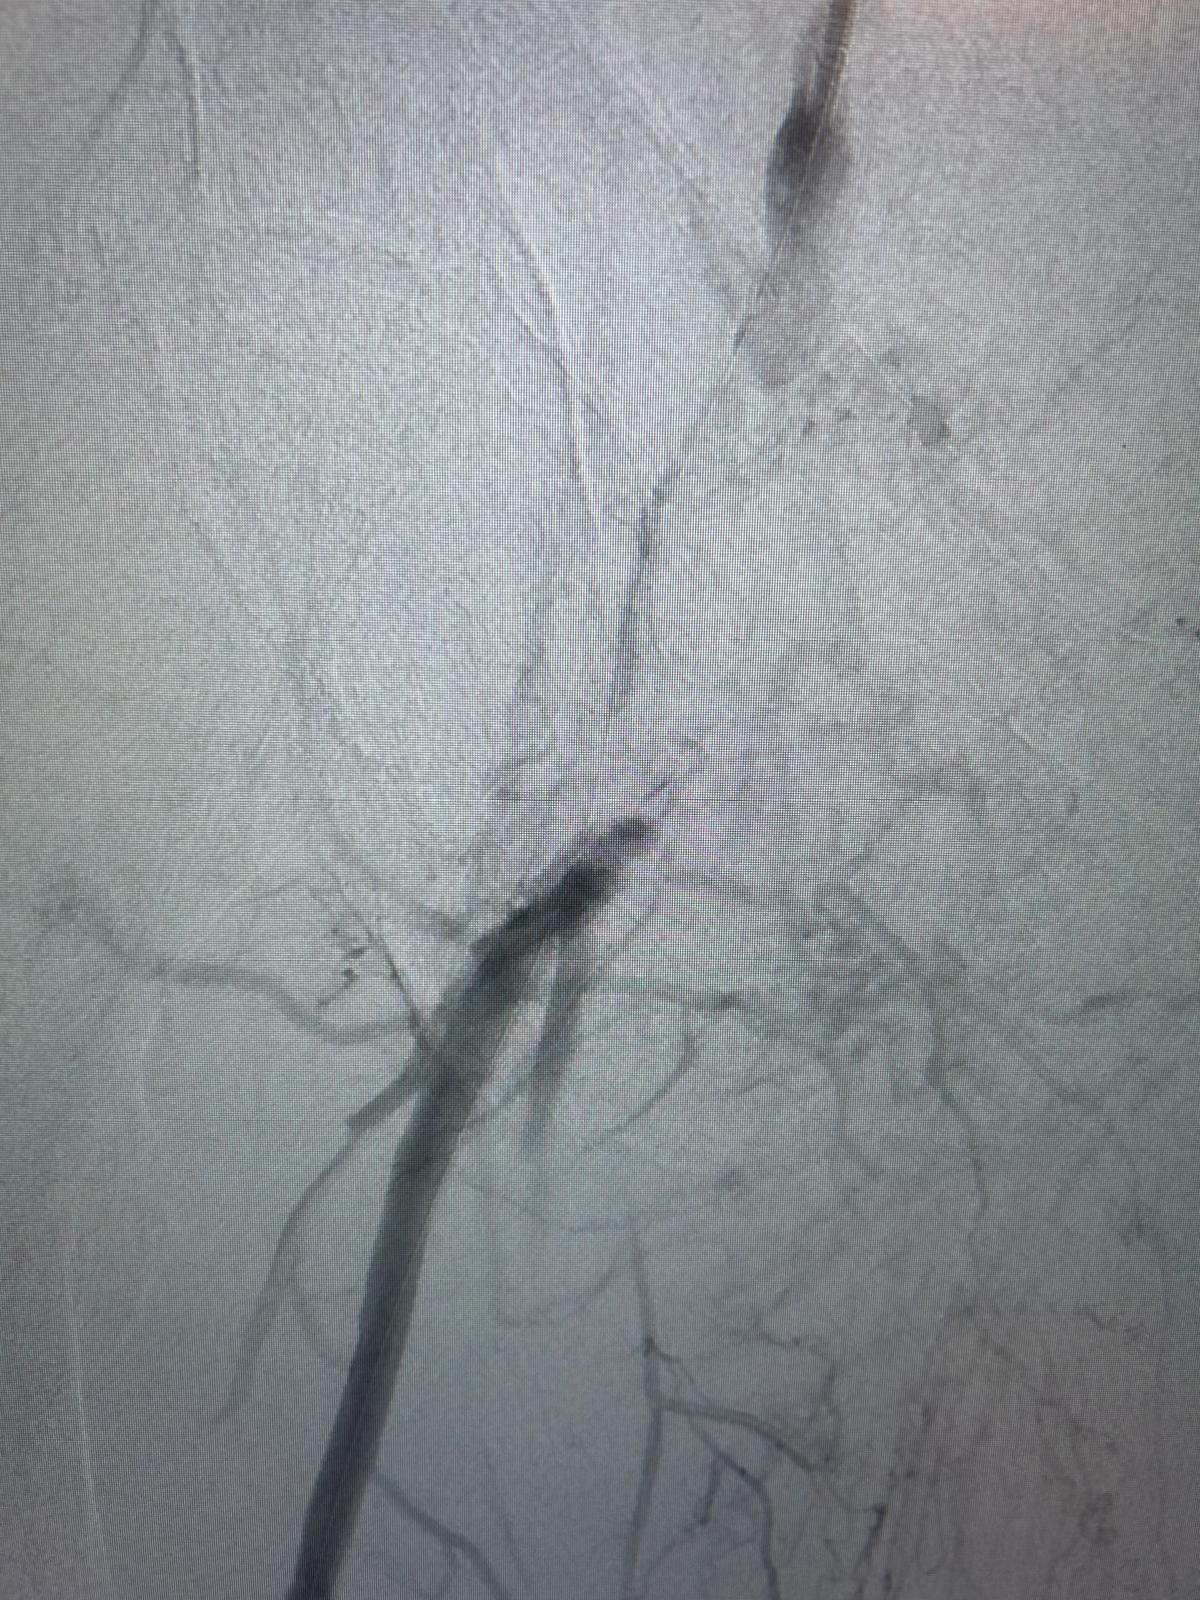

Recanalisation du tronc tibio-fibulaire et de l'artère tibiale postérieure grâce au nouveau ballon actif 0.014 LITOS 3x80mm inflaté à 12 ATM pendant 2,5min.

Mise en place d'une endoprothèse couverte courte au niveau de l'artère poplitée rétro-articulaire (P2).

Excellent résultat persistant de la recanalisation endoluminale des artères jambières sur le contrôle per-opératoire 15 min après la fin de la recanalisation.

Image de spasme de l'artère tibiale postérieure en aval traitée par une injection intra-artérielle de 3mg de Risordan. Disparition immédiate du spasme.